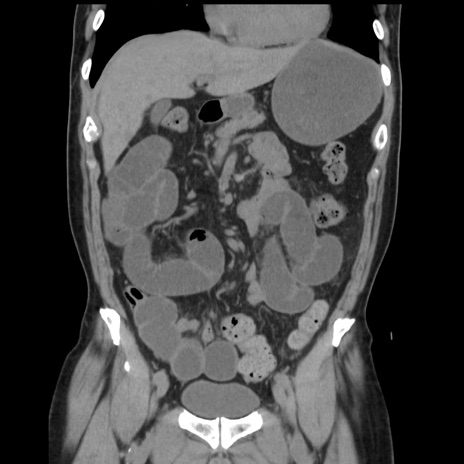

症例16(冠状断像)

【症例】 70歳代男性

【主訴】 腹痛、嘔吐

【現病歴】 約1ヶ月前より間欠的に腹痛と嘔吐あり、当院消化器内科を受診したところCTで多発する肝臓のLDAを指摘され、精査中であった。以降は消化器症状は安定していたが、2日前より嘔気と腹痛があり、同日より排便・排ガスが消失した。改善認めず、 本日、救急外来を受診した。

【既往歴】 大腸ポリープ切除後。

【身体所見】意識清明・会話良好、BT 36.3℃、BP 127/80mmHg、 P 80bpm、腹部:膨満あり、平坦・軟、上腹部正中および下腹部正中に圧痛あり、反跳痛なし、筋性防御なし。

【データ】WBC 7200、CRP 0.77